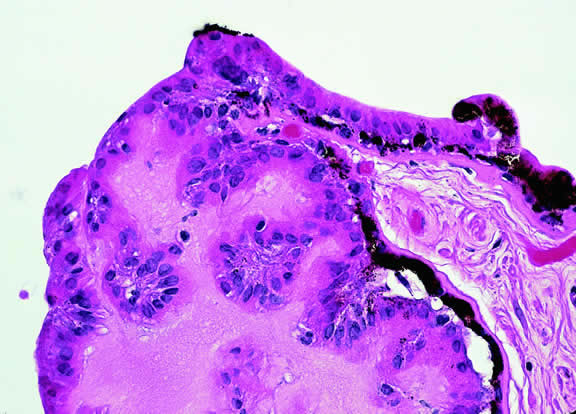

Iris melanoma is relatively rare, constituting between 4% to 15% of uveal melanomas in various series.93 The studies with higher reported incidences may reflect inclusion of nevi. Iris melanomas differ in some respects from tumors of the posterior segment. Most are low-grade spindle cell tumors (Fig. 43). However, iris melanomas with epithelioid cells occasionally are encountered (Fig. 44). Many pigmented iris tumors actually are nevi,94 and relatively few of these enlarge when observed. Several studies have shown that the risk of enlargement in 5 years is only 5% to 6% after a subset of promptly treated lesions is excluded.95,96 One study showed that iris tumors are likely to be considered melanomas and be treated promptly if the basal diameter is greater than 3 mm, pigment dispersion or prominent tumor vascularity are present, the intraocular pressure is elevated, or there are tumor-related symptoms.95 The mean age of patients with iris melanomas is about 10 years younger (age 43 years) than the age of patients with posterior segment melanomas.97 The prognosis of iris melanoma is also relatively favorable compared with tumors of the posterior segment. Shields and coworkers97 studied 169 patients with histologically confirmed iris melanoma and found that distant metastases developed in 5% at 10-years follow-up. The relatively small size of most iris melanomas probably is a major factor in their good prognosis. The prognosis of iris melanomas actually may be similar to posterior segment tumors of similar size and cell type. Diffuse iris melanomas that cause heterochromia iridis and secondary glaucoma are a rare but clinically important group of iris tumors.98,99 Many diffuse iris melanomas are higher grade tumors that contain epithelioid cells, which are poorly cohesive and prone to aqueous dispersal. Glaucoma surgery should be avoided in such cases. It invariably fails and puts patients at greater risk for extraocular extension and metastasis.100

Fig. 43. Low-grade spindle cell iris melanoma. Cytology is very bland. Only a few small nucleoli are present. (Hematoxylin-eosin, × 250.)

Fig. 44. Iris melanoma, mixed cell type. Pigmented infiltrate replacing iris stroma contains many epithelioid cells. (Hematoxylin-eosin, × 250.)